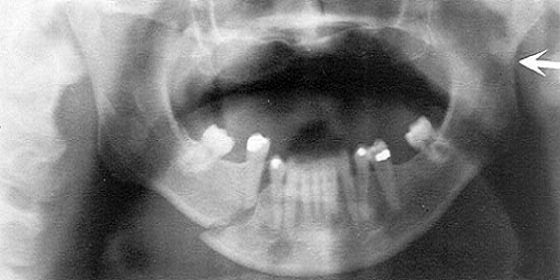

Сразу после перелома костей челюсти и обращения к врачу делается панорамный снимок, показывающий серьезность перелома и помогают спланировать лечение.

После этого из области перелома удаляются все зубы, так как вернуть им функциональность уже не получится. После удаления обломки челюсти собирают вместе и фиксируют при помощи швов и других инструментов и приспособлений, и уже потом накладывают на челюсти шину, чтобы обеспечить срастающимся костям покой.

При прощупывании можно обнаружить только конкретный участок зубного ряда, который является признаком возникновения боли. Чтобы точно определить перелом, необходимо пройти рентгенографию и выполнить снимки в разных проекциях.

Травма является нарушением анатомической целостности кости челюсти, вследствие которого возможен разрыв находящихся поблизости тканей. Диагностируется с помощью рентгеновского обследования, которое необходимо доктору для точного установления диагноза и определения степени тяжести полученной травмы.